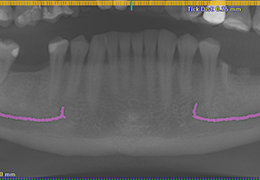

View X-Ray CT & MRI Scans Fast and Easily

Designed for surgeons, Pro Surgical 3D makes it easy to view patient scans quickly. Pro Surgical 3D facilitates the optimal 3D treatment and assessment workflows based on X-ray CT and MRI scans – and best of all, it’s FREE!

Traditional multi-planar slicing

Multi-planar slicing.

Oblique slicing.